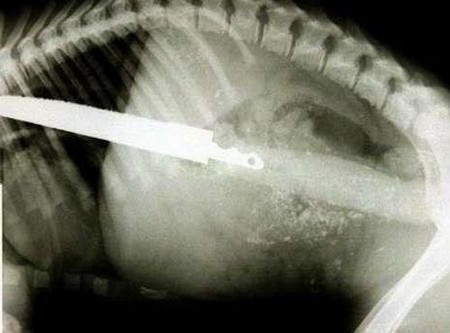

İnanılmaz röntgen filmleri - Resim: 1

İnanılmaz röntgen filmleri görenleri çok şaşırtıyor